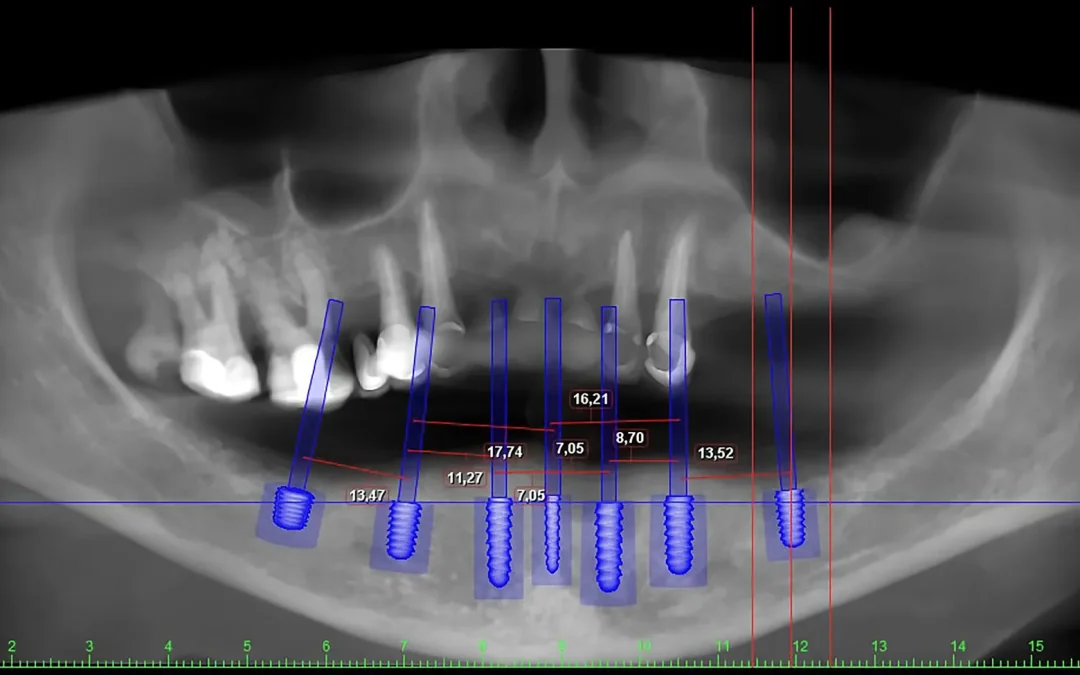

Nel nostro studio a Brescia abbiamo trattato con successo numerosi casi complessi. In uno di questi, una paziente adulta è stata sottoposta a un trattamento linguale di 20 mesi, con l’estrazione di due premolari superiori. Oggi, osservando il suo sorriso, non si nota alcuna traccia di denti mancanti, ma solo un’armonia perfetta.